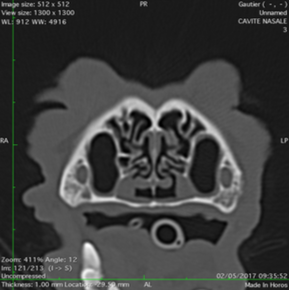

Les scanners du nez

Le scanner est l'examen de choix pour une exploration nasale complète... La cavité nasale de nos carnivore est formée de nombreux plis de muqueuses, appelés volutes, qui vont permettre un odorat très développé. Les lésions ne sont pas rareset se repartissent de la manière suivnte:

Scanner Normaux

Scanners nasaux anormaux